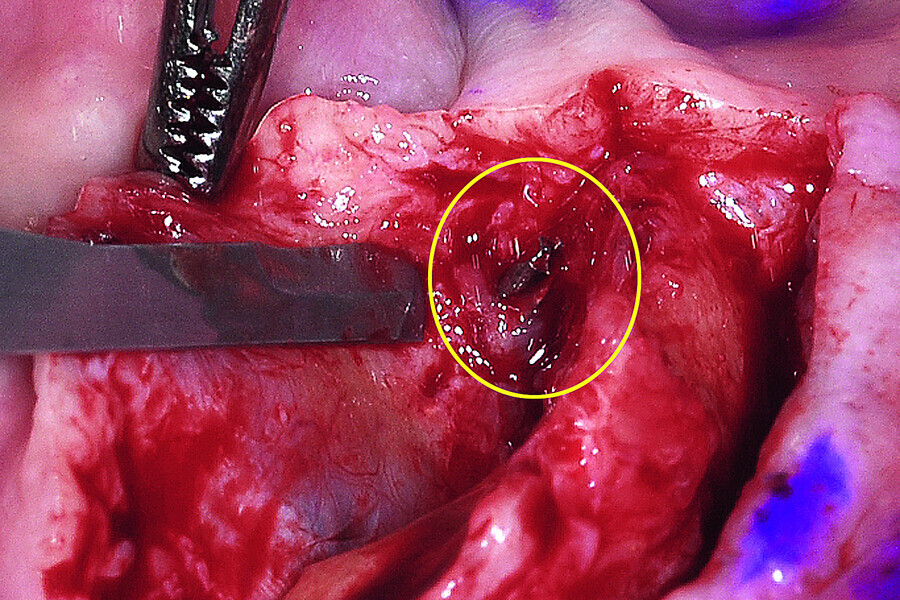

Fig. 14: The broken drill was located lingual to the bony crest of the mandible.

Fig. 15: The anterior symphysis revealing the anterior ‘hollow’ symphysis.